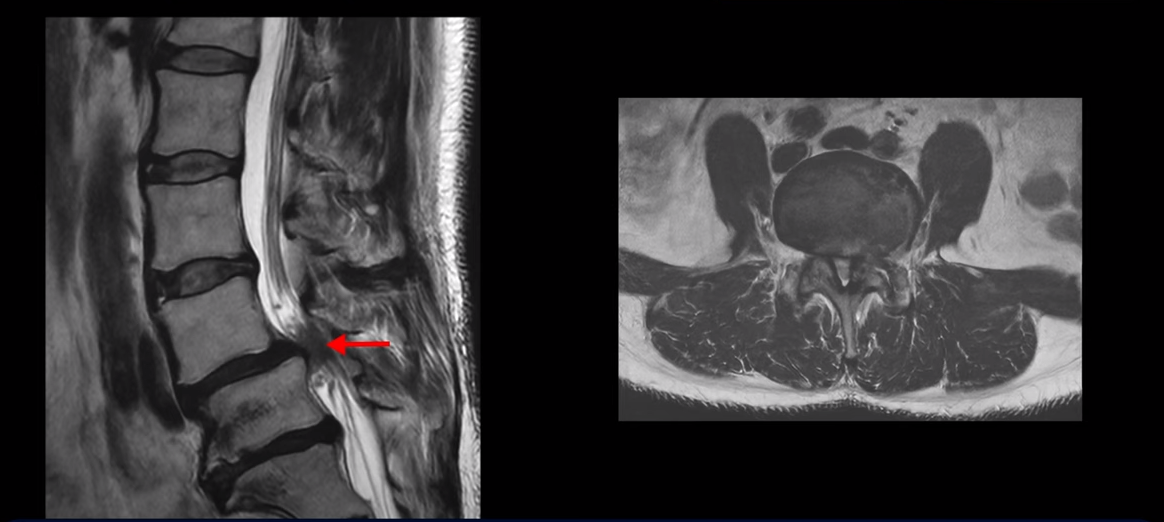

제가 먼저 이 환자분 MRI를 보면서 설명 드린 후 이분 말씀 더 들어보겠습니다. 보시다시피 두 마디가 심하게 퇴행되어 있고

4번 5번에는 척추뼈가 밀려나간 전방전위증이 있습니다.

4번 5번에 심한 중심성 협착도 있습니다.

양쪽 신경 가지가 빠져 나가는 추간공도 왼쪽 오른쪽 모두 좁아져 있습니다.

5번 1번에는 가운데로는 디스크가 밀려나와 있습니다.

이건 아주 오래된 퇴행성디스크로 보입니다. 그래서 이 환자분은 양쪽 엉덩이와 다리가 모두 저리고 아픈 게 양쪽 추간공 문제 때문일 수도 있고 중심성 협착 때문일 수도 있습니다. 퇴행성디스크 때문에 아플 가능성은 상대적으로 적어보입니다.

이 분도 수년간 신경주사와 도수치료를 받으며 버티다가 올해 2월에 아버님 장례식 때문에 무리하면서 다리 증상이 심해집니다. 병원에서는 뼈가 밀려 나가 있으니 나사를 박는 수술을 해야 한다고 하는데 저희 모커리에서는 어떻게 이런 분들이 수술 없이 치료가 가능하다고 하는 걸까요?